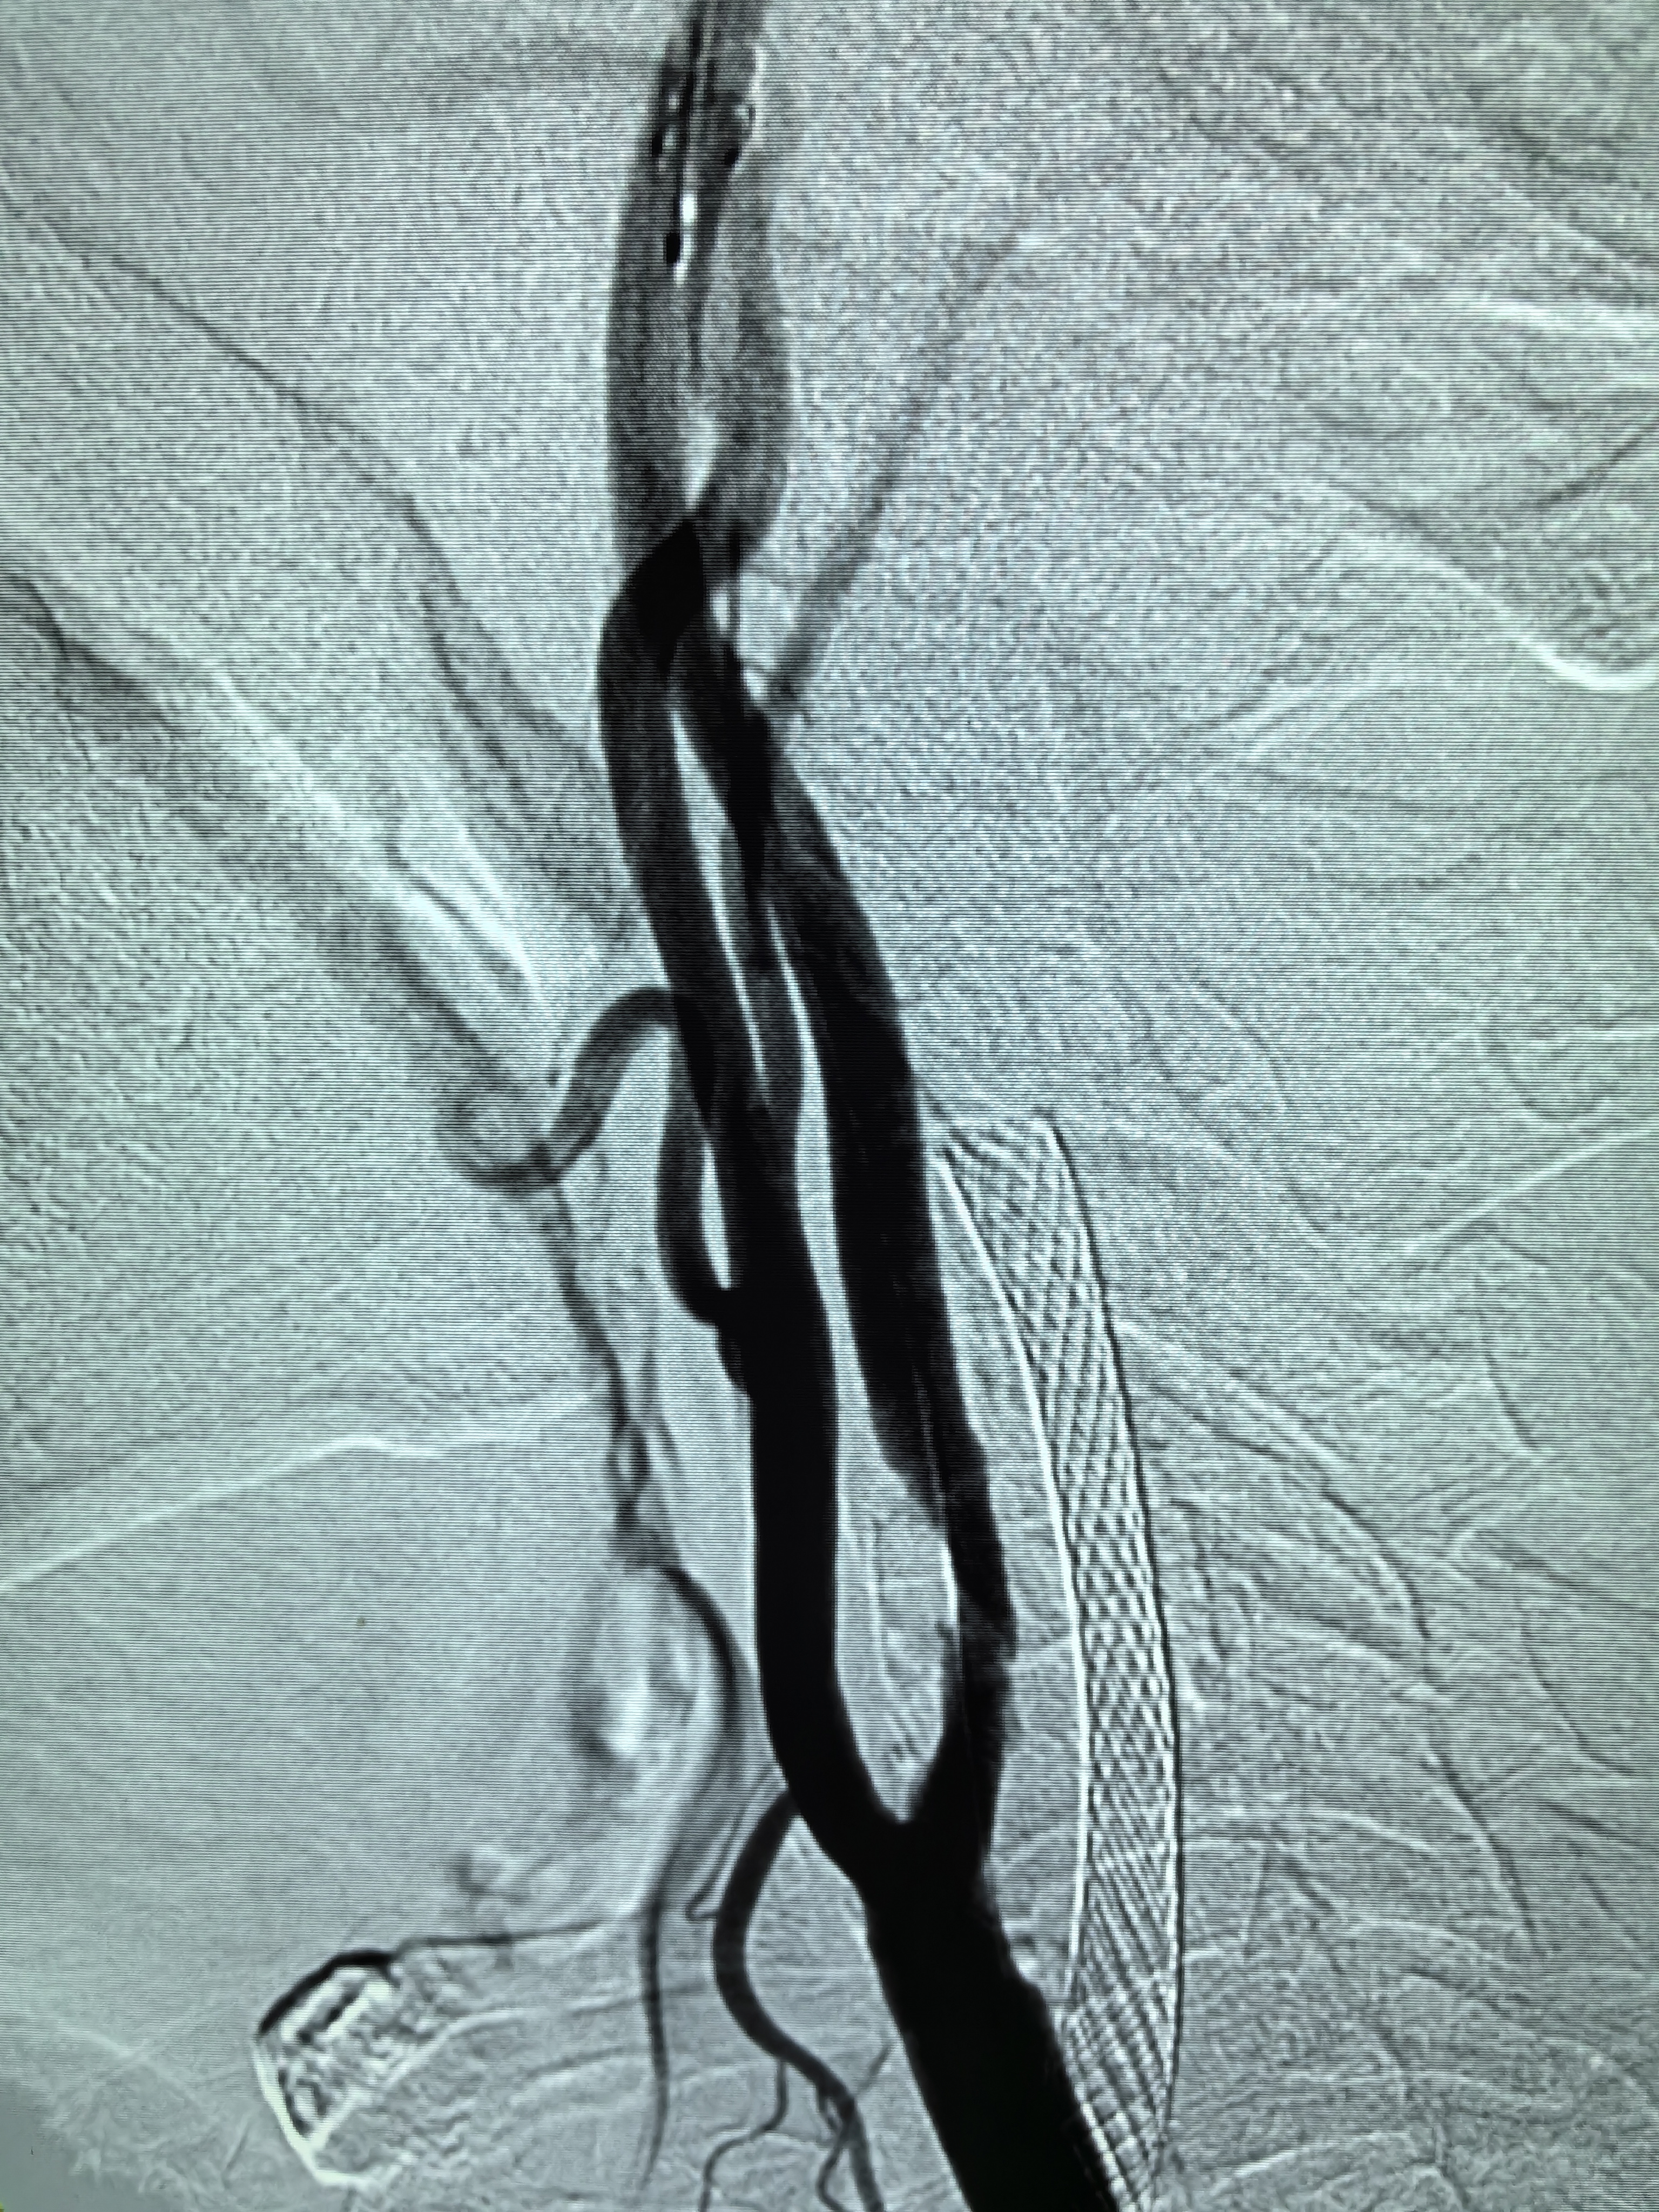

患者男性,70岁,体检发现双侧颈内动脉重度狭窄,1月前行右侧颈内动脉支架成形术,现为治疗左侧颈内动脉狭窄入院。既往高血压病史30年,口服硝苯地平控释片降压,血压控制130/80mmHg。

1、本例患者老年男性,双侧颈内动脉重度狭窄,治疗采取分期处理,间隔4周。

2、左侧颈内动脉从CTA看狭窄合并软斑,具备介入治疗指征。